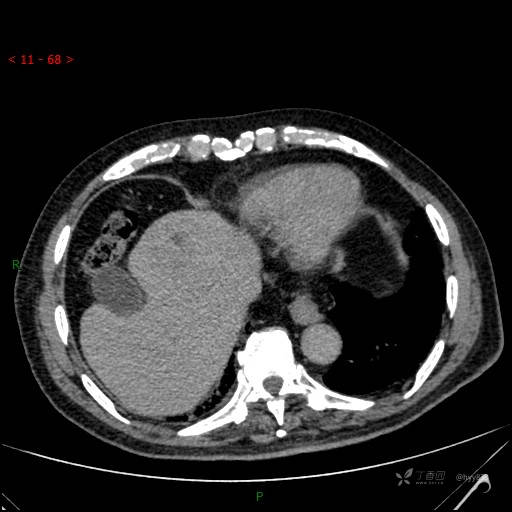

增强动脉期

img